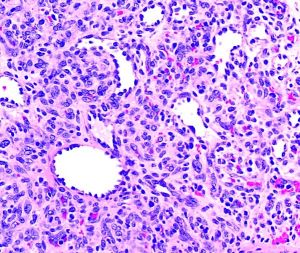

On gross examination the specimen appears as a fleshy, red hemorrhagic, polypoid or pedunculated nodule. Histologically, pyogenic granulomas appear with lobular vascular proliferations and branching endothelium-lined vessels with inflammation and edema resembling granulation tissue. The overlying epidermis may show ulceration if the lesion has bled and has acanthosis, hyperkeratosis, and hypergranulosis. In mature lesions, a fibromyxoid stroma divides the pyogenic granuloma into lobules.[15] In a regressing pyogenic granuloma, extensive fibrosis can be observed.[15]

Relevant immunohistochemical stains are directly related to its vascular origin, thus PG would be positive for CD34, CD31, Factor VIII, SMA, while negative for HMB-45, which would differentiate the lesion from melanoma.[16]